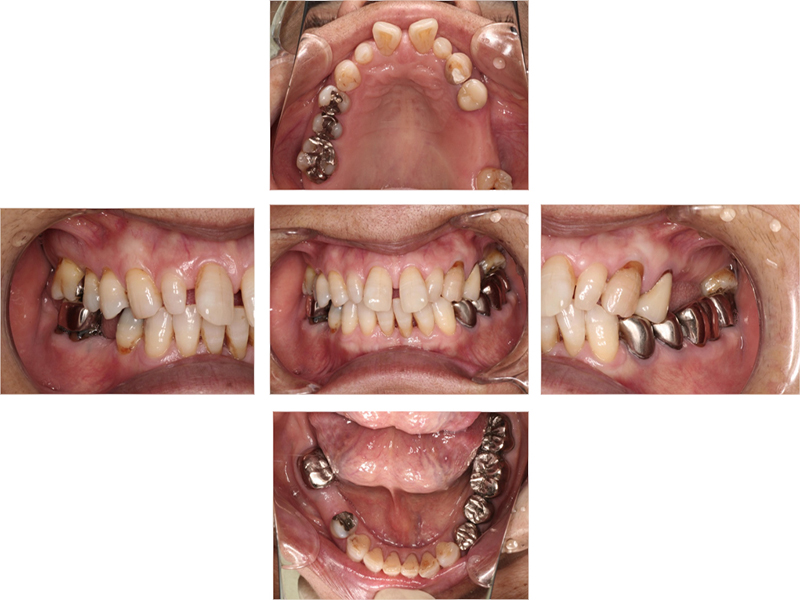

初診